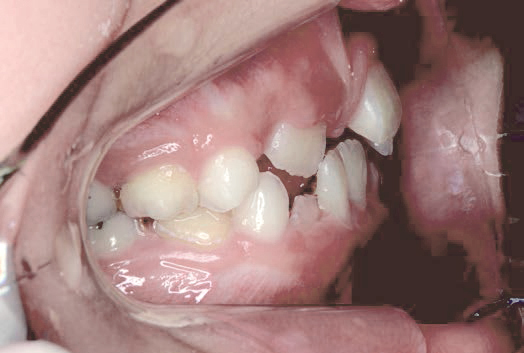

Before

歯がガタガタに並んでいて、前歯の真ん中の位置が少し左にずれていました。

奥歯が生えるためのスペースが足りず、永久歯が生えて来られない状況が確認できました。

また、飲み込むとき下くちびるに力が入ってしまうクセが見られ、お顔全体の成長が遅れている様子が確認できました。